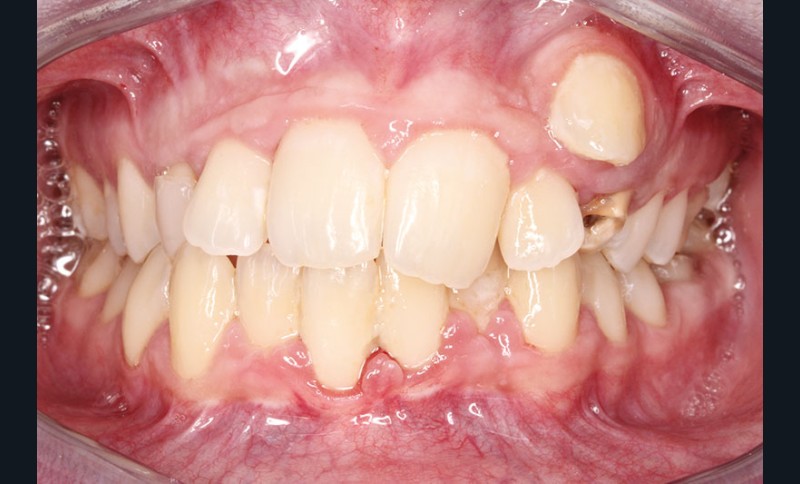

• Endo-buccal : Younesse présente un contrôle de plaque dentaire insuffisant, la persistance de 53 et 63, des soins en cours de réalisation sur 26 et 36, un encombrement maxillo-mandibulaire avec infravestibulotopie de 23 et une suspicion d’inclusion de 13 sur un schéma de Classe II subdivision droite (fig. 3 à 7).

L’examen parodontal révèle une gingivite généralisée ainsi qu’un parodonte très fin et une absence de profondeur vestibulaire.